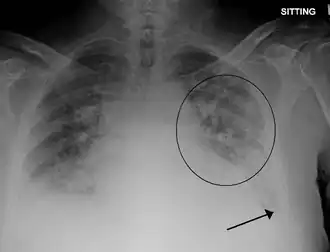

Edema pulmonar (do grego οἴδημα, transbordar) é o acúmulo de fluido nos pulmões diminuindo a eficiência das trocas gasosas (O2 e CO2) podendo resultar em insuficiência respiratória. É uma das emergências médicas mais frequentes e pode ser fatal em poucas horas. É uma consequência comum de problemas cardíacos, vasculares ou por distúrbios da pressão pulmonar.